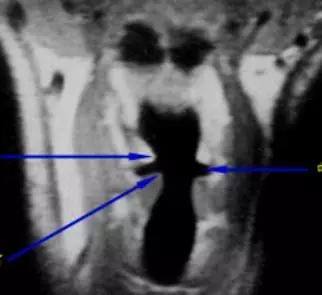

3、MRI

- 冠状面显示声带、室带、喉室、胸廓入口等情况较好;

2、CT、MRI检查